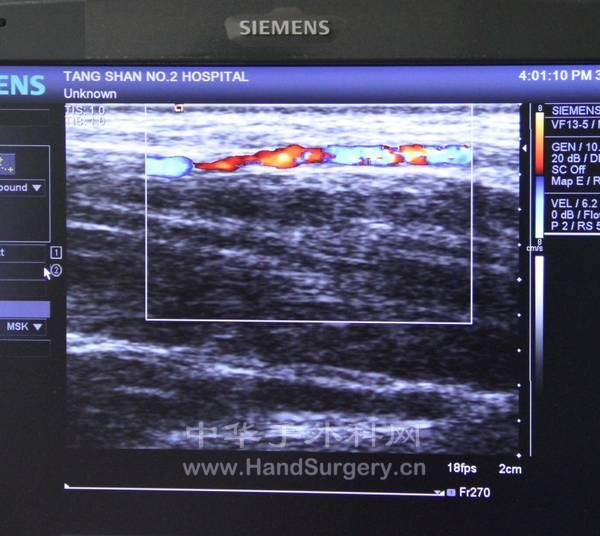

顺便做了掌背动脉的彩超

6.jpg